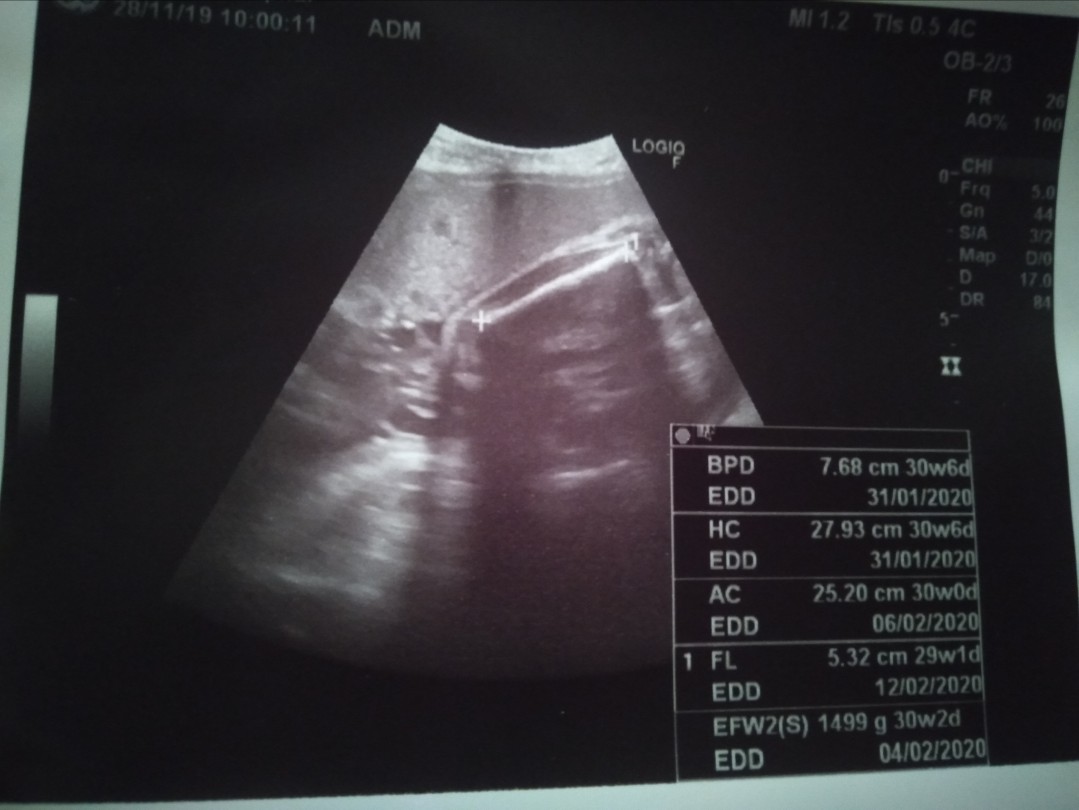

อัลตร้าซาวด์

แม่ๆคนไหนคลอดเดือนกุมภาพันธ์63บ้างคะ วันนี้ไปซาวด์มาหมอบอกว่าได้ลูกสาว ดีใจค่ะ แต่ดูใบซาวไม่ถนัดค่ะ